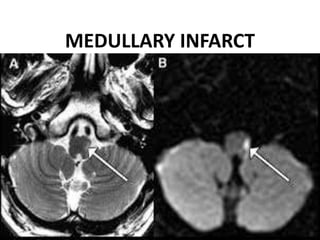

MEDULLARY INFARCT